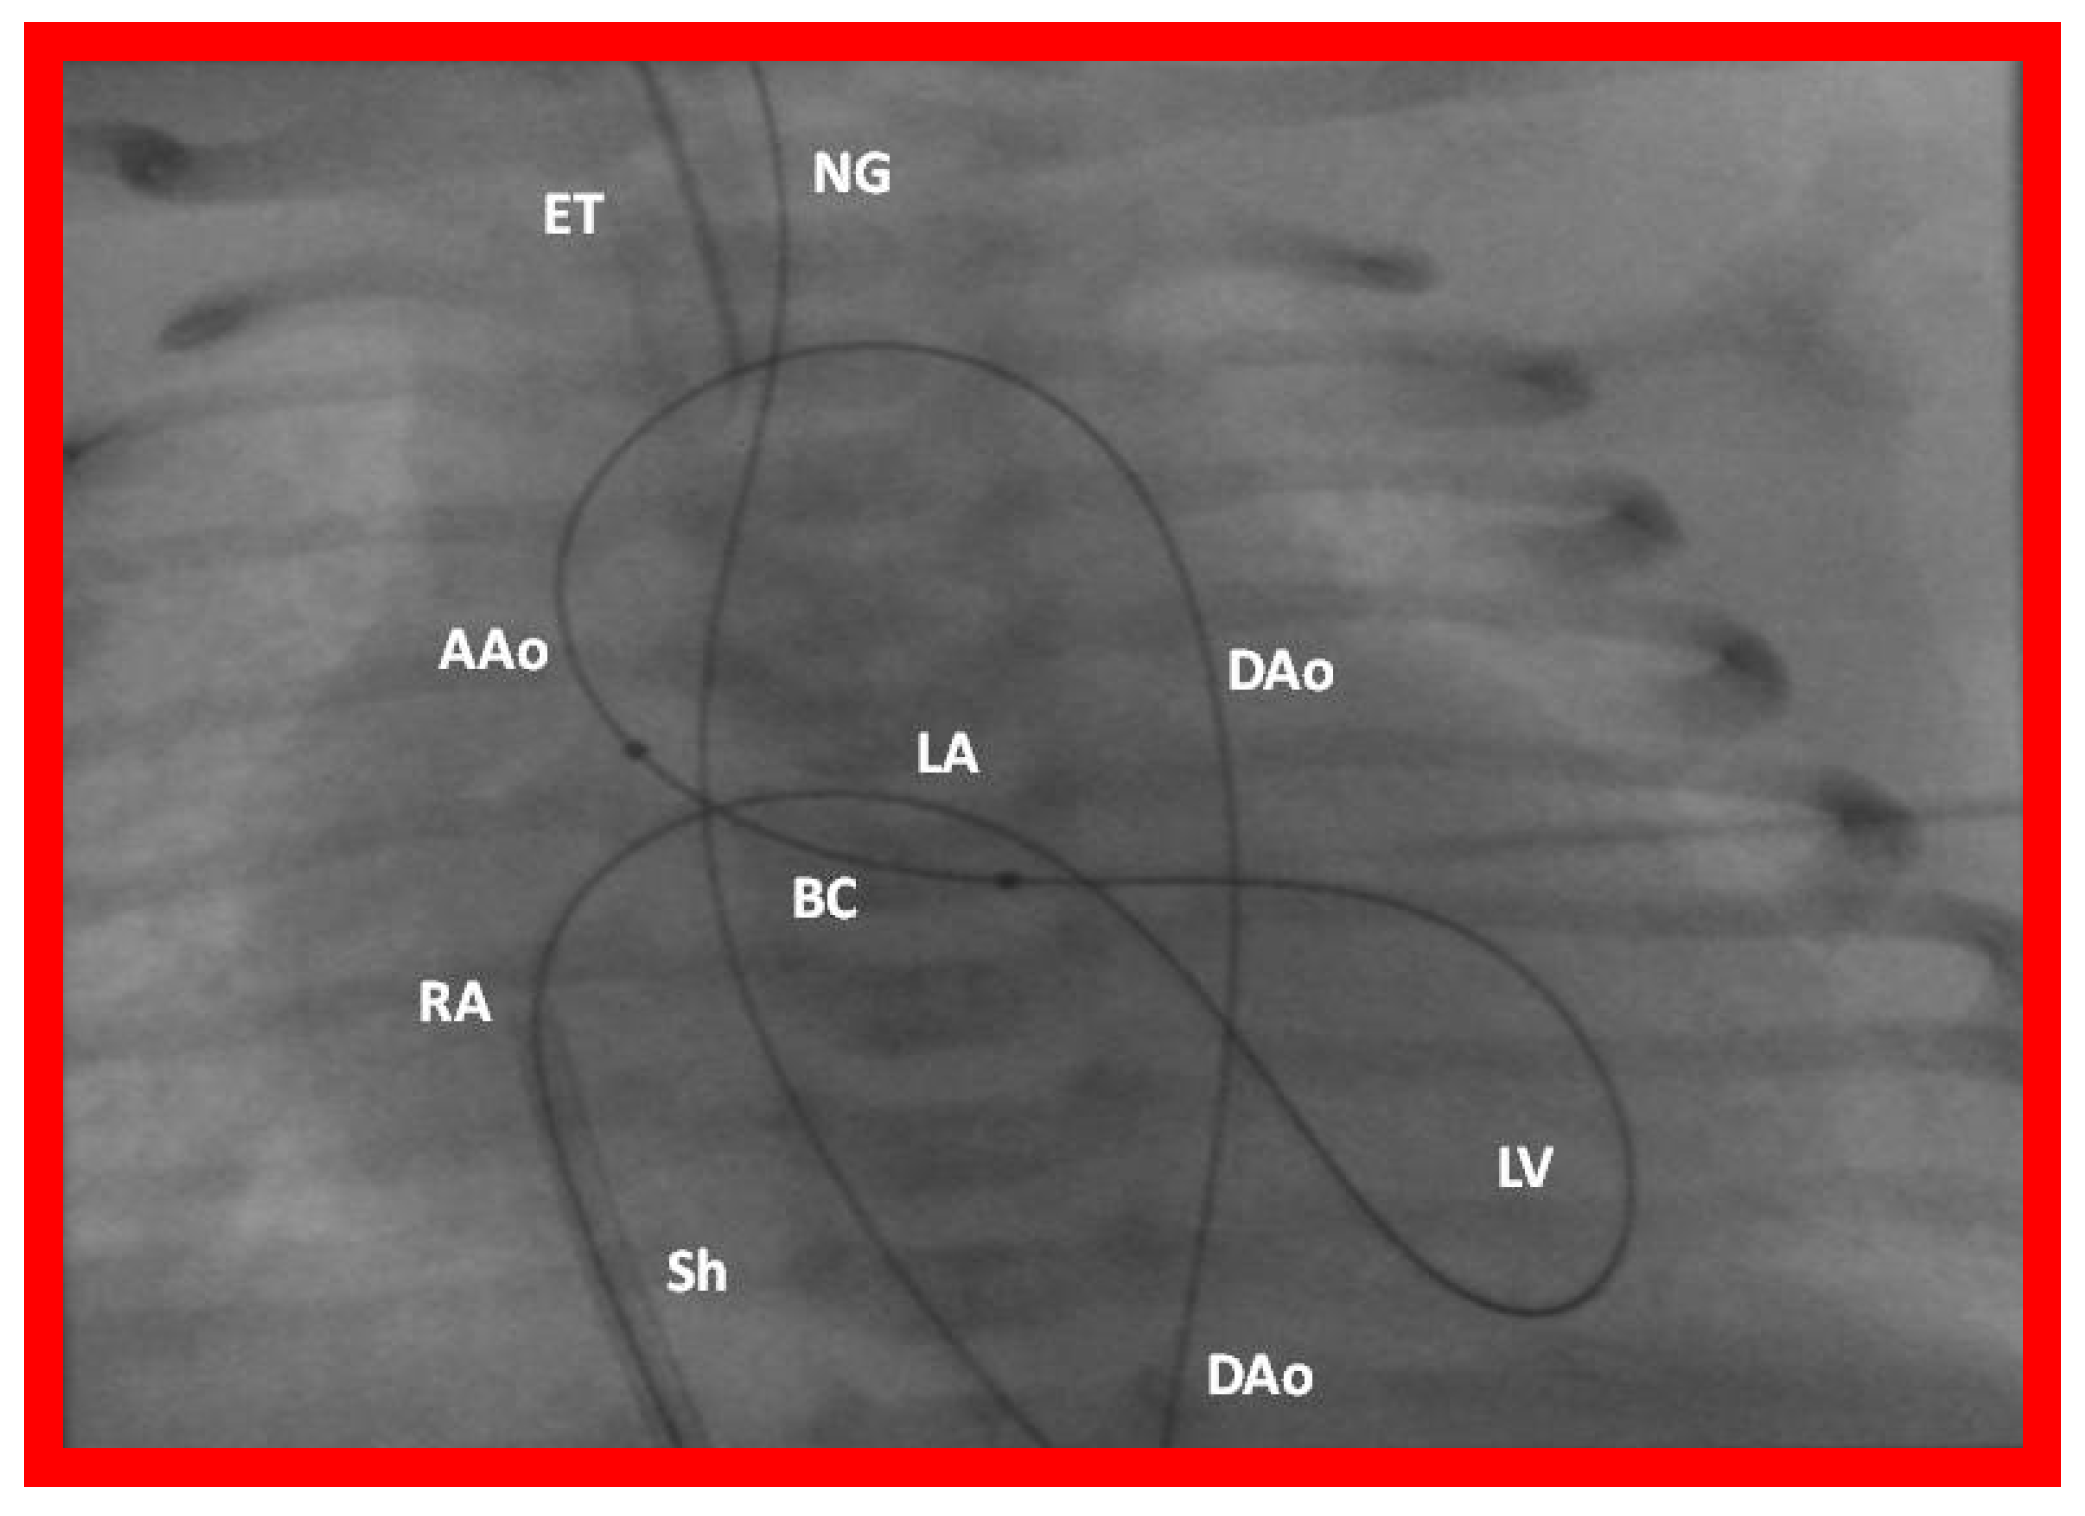

- Rao, P.S.; Jureidini, S.B. Transumbilical venous anterograde, snare-assisted balloon aortic valvuloplasty in a neonate with critical aortic stenosis. Catheter. Cardiovasc. Diagn. 1998, 45, 144–148. [Google Scholar] [CrossRef]

- Rao, P.S. Anterograde balloon aortic valvuloplasty in the neonate via the umbilical vein. Card. Cardiovasc. Interv. 2003, 59, 291–292. [Google Scholar] [CrossRef] [PubMed]

- Rao, P.S. Role of interventional cardiology in neonates: Part II-Balloon angioplasty/valvuloplasty. Neonatol. Today 2007, 2, 1–12. [Google Scholar]